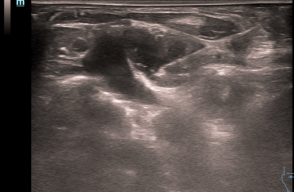

甲状旁腺结节术前细针穿刺

整个手术过程可控性强,能有效避开喉返神经、周围血管及甲状腺组织,避免误伤风险。患者仅接受局部麻醉,全程耐受度良好,未出现明显不适,术后仅留下针眼大小的创口,无需缝合。